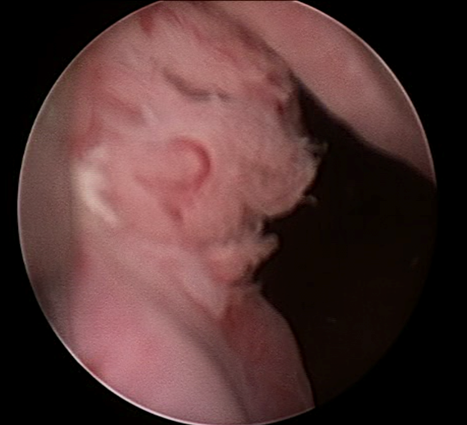

Se realiza uretrocistoscopía encontrando una tumoración en el tercio proximal de la uretra, de la cual se realizó una resección transuretral, encontrando que provenía del interior de un divertículo (Imágenes 2 y 3).